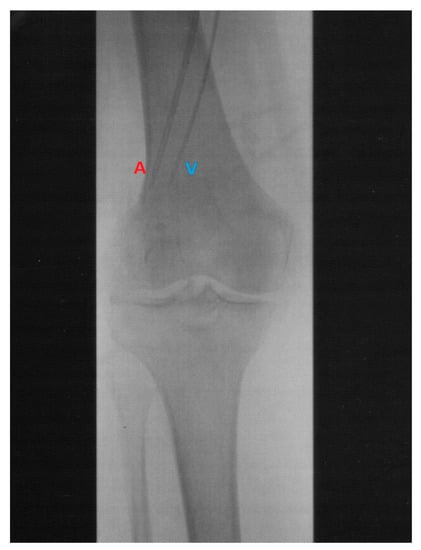

| Hyperthermic Isolated Limb Perfusion | Isolated Limb Infusion |

|---|---|

| Technically complex | Technically simple |

| Open surgical exposure of vessels for catheter insertion | Percutaneous vascular catheter insertion in radiology department |

| 4 to 6 h duration | Approximately 1 h |

| Perfusionist and ancillary staff required | No perfusionist required and fewer total staff |

| Complex and expensive equipment needed | Equipment requirements modest |

| Magnitude of procedure excludes patients | Well tolerated by medically compromised, frail and elderly patients |

| Not possible in occlusive vascular disease | Can be performed selectively in occlusive vascular disease |

| Technically challenging to perform a repeat procedure | Not difficult to perform a repeat procedure |

| Systemic metastases normally a contraindication | Systemic metastases not a contraindication |

| Higher perfusion pressures predispose to systemic leakage | Low pressure system, effective vascular isolation with tourniquet |

| Limb tissues oxygenated, with normal blood gases maintained | Progressive hypoxia and acidosis |

| Hyperthermia (>41 °C can be achieved) | Usually not possible to raise limb temperature above 40 °C |

| General anesthesia (GA) required | Possible with regional anaesthesia, GA preferred. |